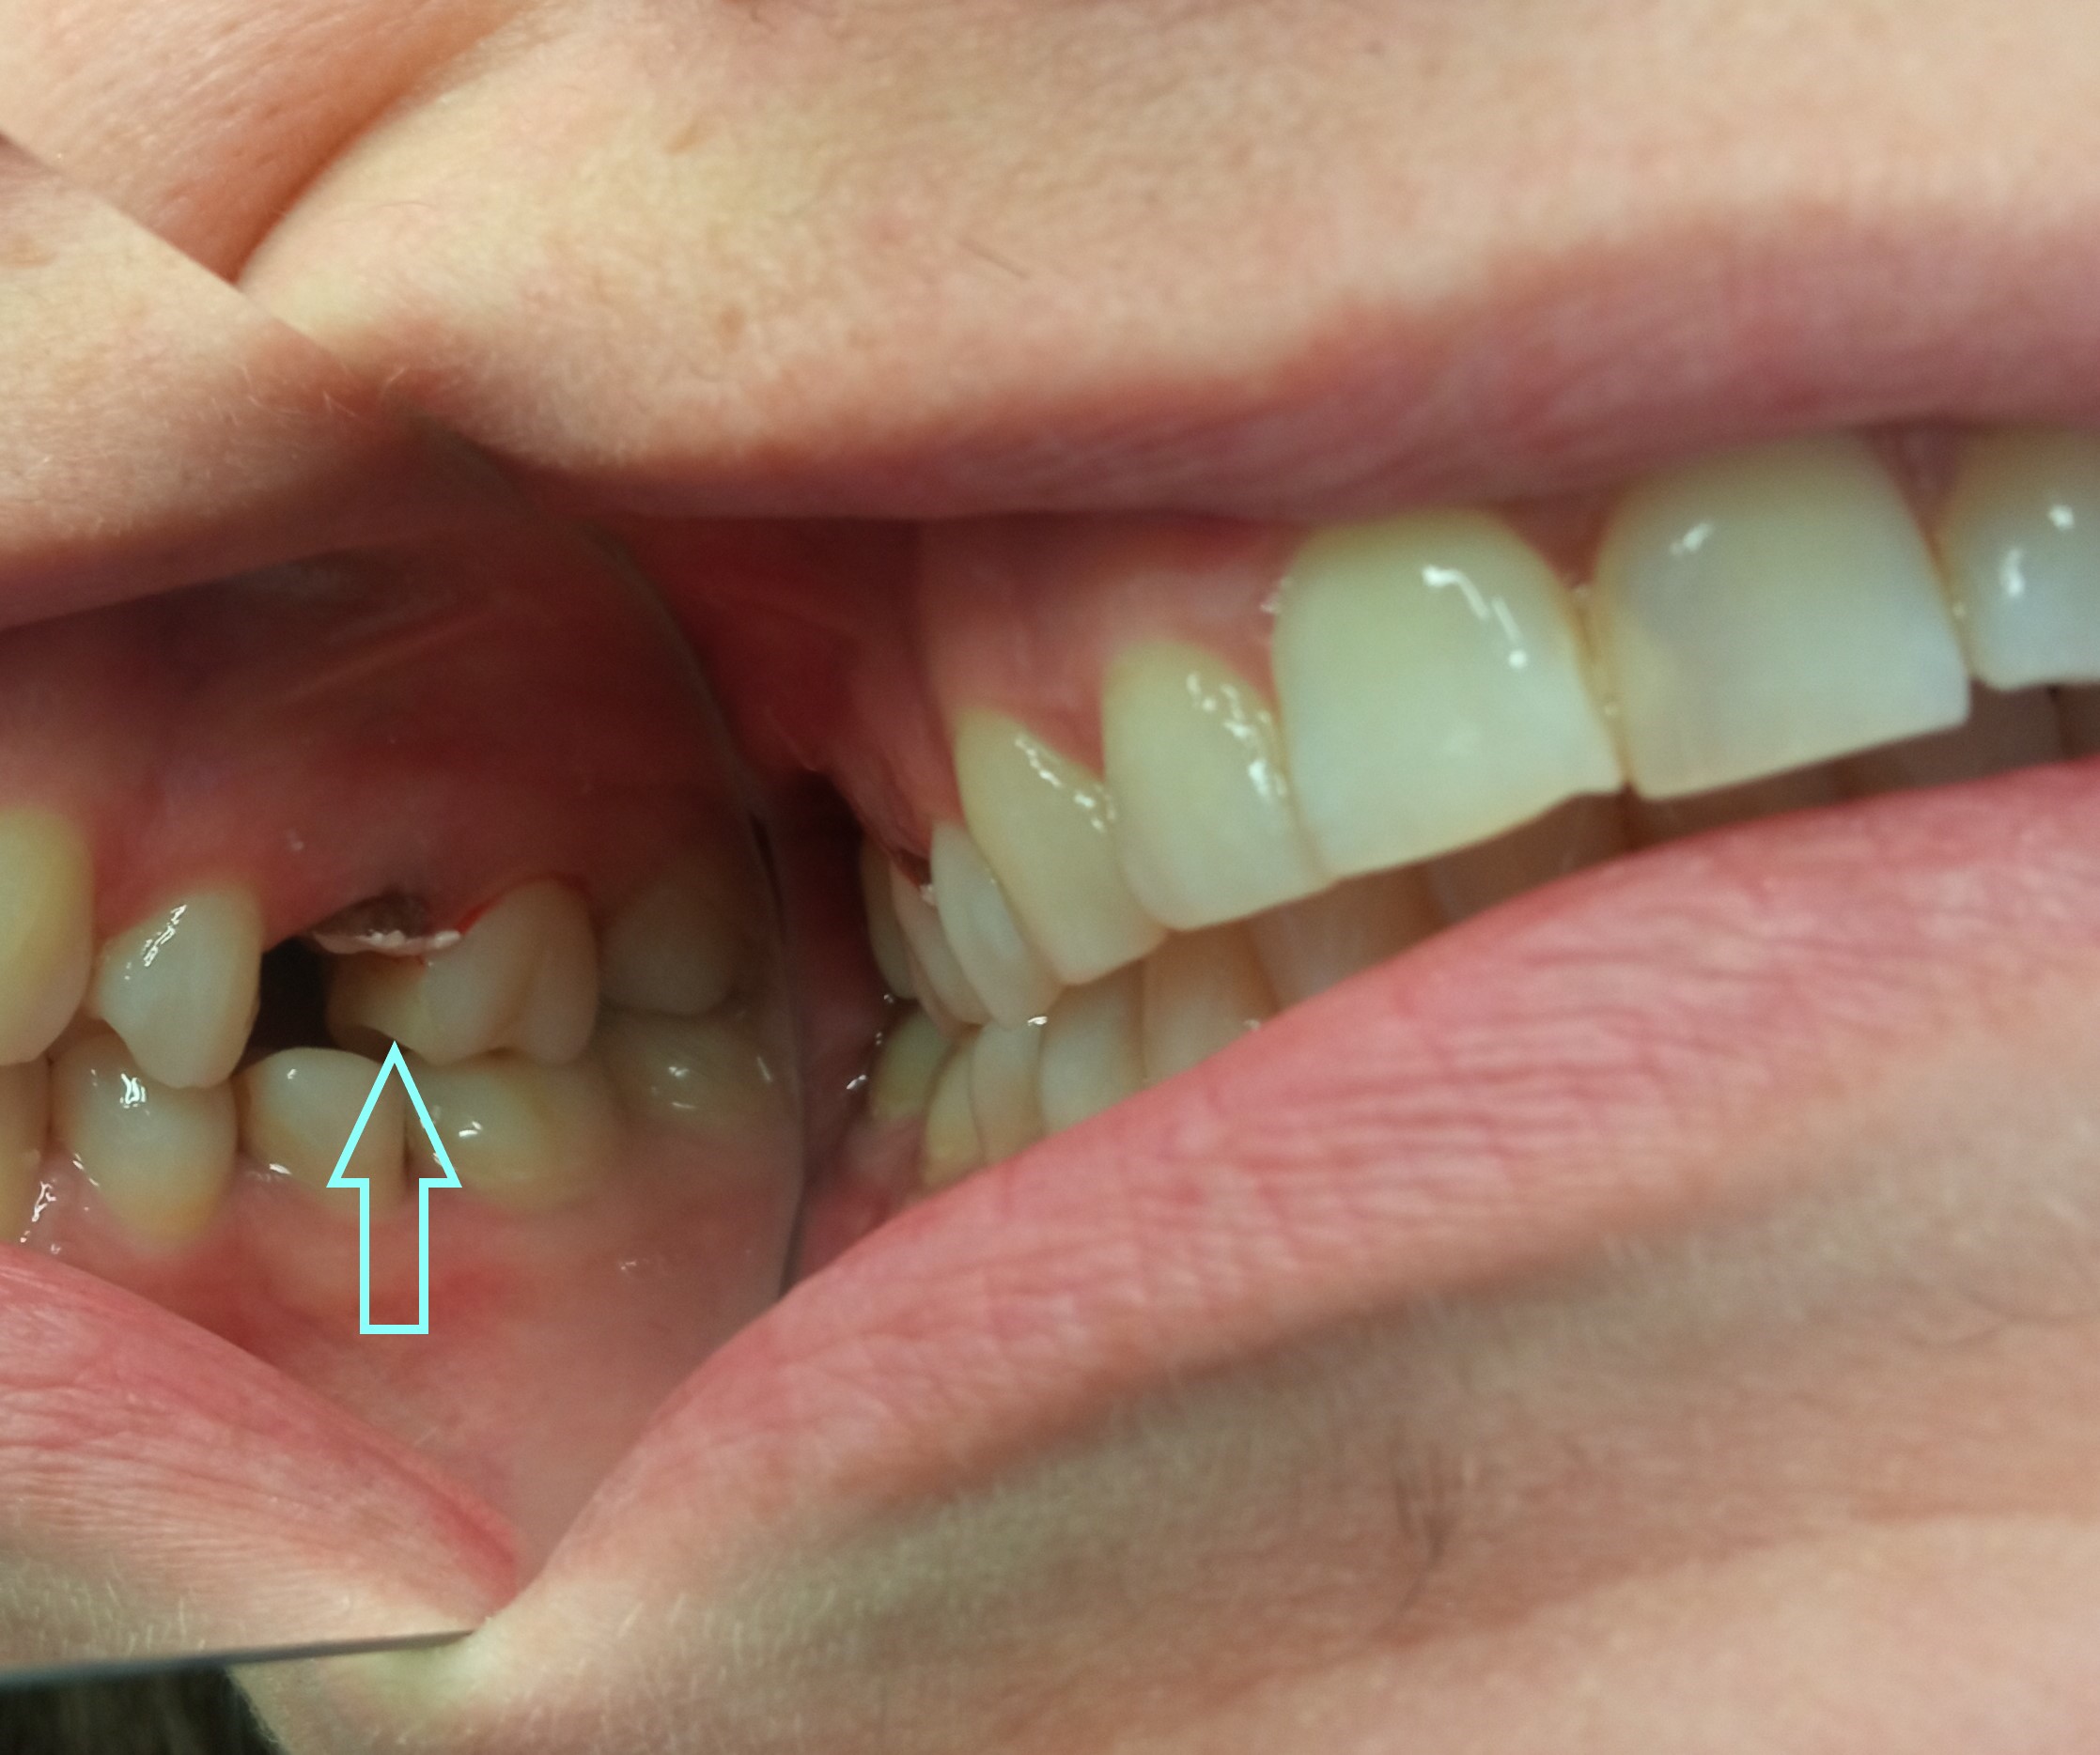

Ο πρώτος γόμφιος στην αριστερή πλευρά της κάτω γνάθου είχε απονευρωθεί στο παρελθόν. Ο ασθενής δεν θέλησε να καλύψει το δόντι με θήκη, ώστε να είναι πλήρως προστατευμένο με αποτέλεσμα το δόντι να σπάσει (όπως φαίνεται στην αρχική εικόνα). Η λύση θεραπείας ήταν η κατασκευή στεφάνης δοντιού, αφού προηγουμένως το δόντι τροχίστηκε καταλλήλως και ο οδοντοτεχνίτης κατασκεύασε την ολοκεραμική θήκη ζιρκονίου.

Το δόντι είναι πλέον πλήρως προστατευμένο και μπορεί να αντέξει στο πέρασμα των χρόνων.

ΠΡΙΝ